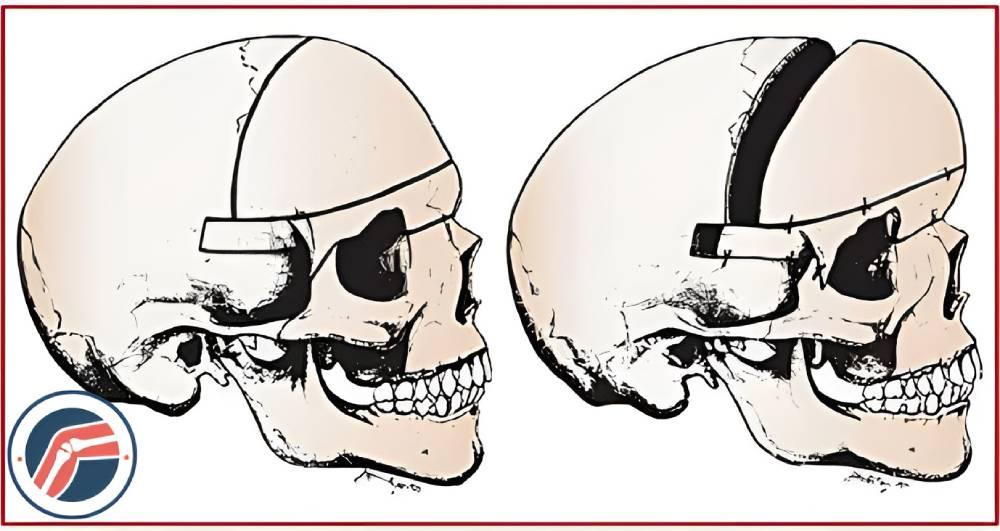

جراحی کرانیوسینوستوز باز

بازسازی طاق جمجمه (CVR): در این روش جراح تکههایی از جمجمه را در نزدیکی درز بسته شده برمیدارد و به آن شکل میدهد تا فضایی برای رشد مغز فراهم شود. این نوع جراحی برای موارد شدید اختلال و زمانی که چند درز بسته شده در جمجمه وجود دارد استفاده میشود.

CVR ممکن است در کل جمجمه یا در بخشهای جداگانه انجام شود.